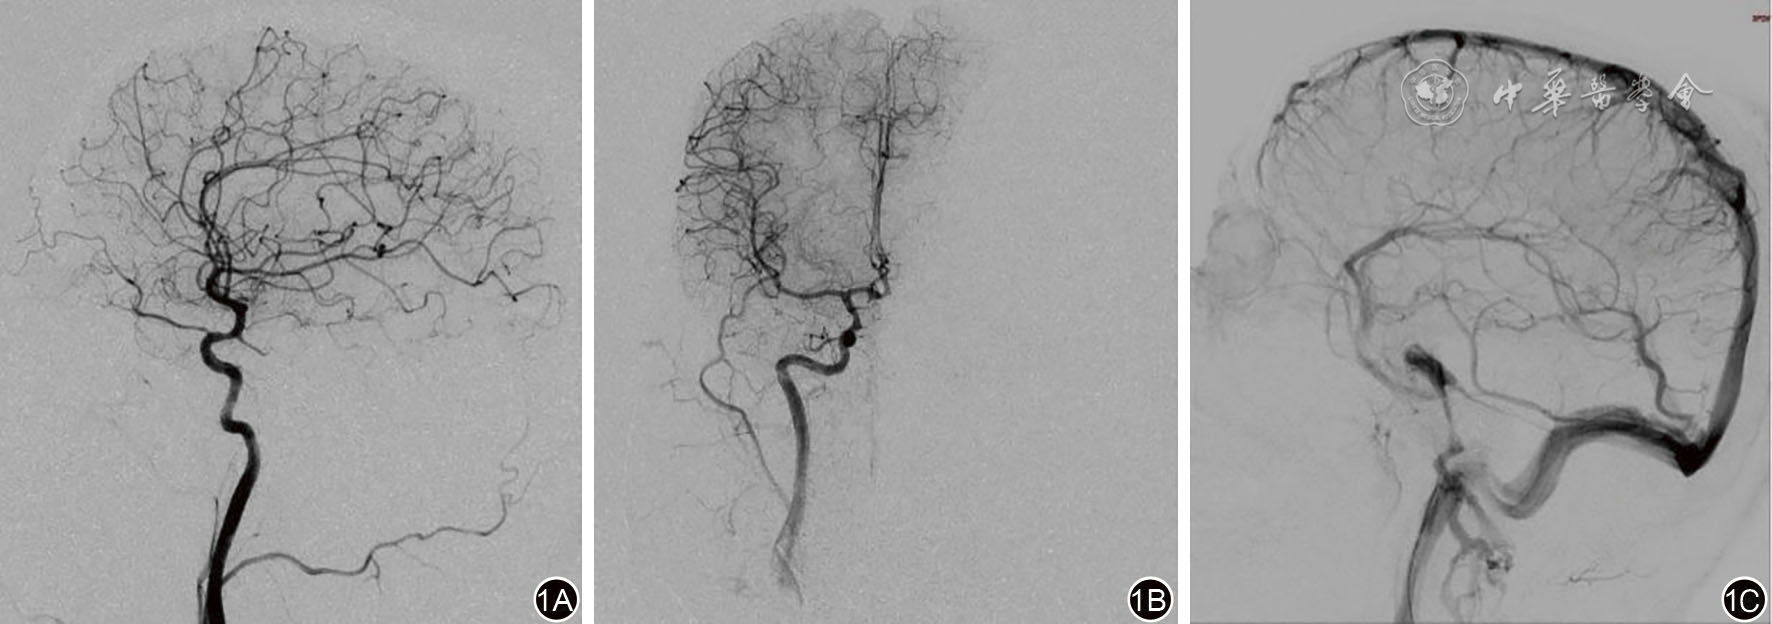

图1 右侧颈动脉造影及岩下窦静脉采血 1A、1B:右侧颈动脉造影正位、侧位图,可见右侧颈内动脉主干及其主要分支动脉走形自然,未见明显异常血管;1C:静脉期见右侧岩下窦及海绵窦显影,将导管插入右侧岩下窦(箭头标示处)后取血。